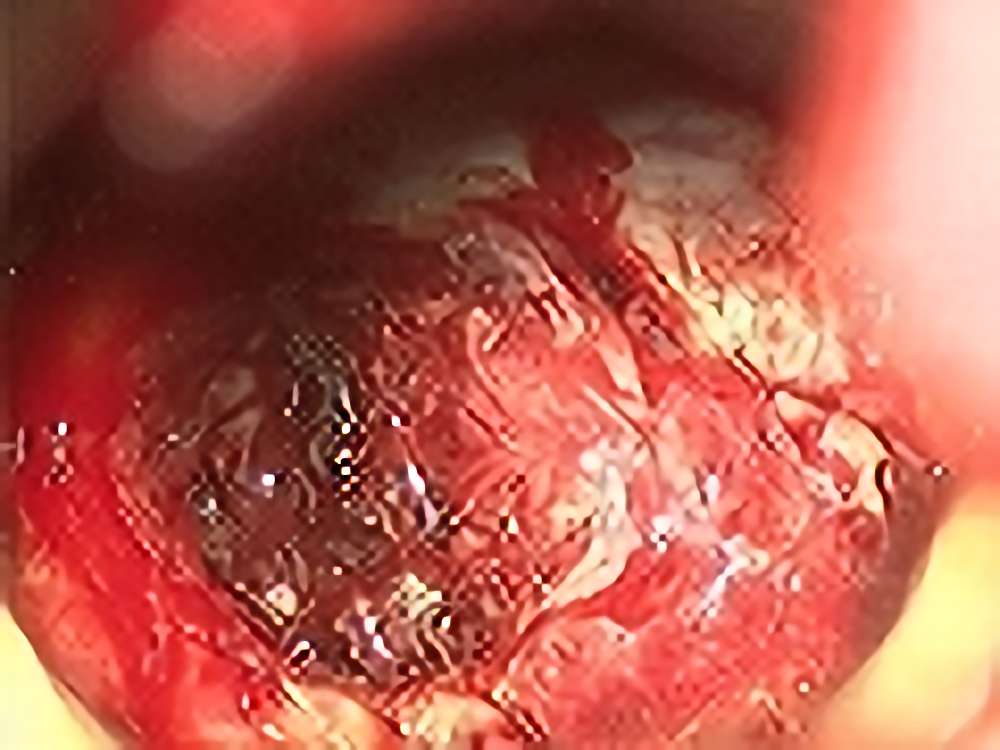

'13年12月

50代

転移性脳腫瘍

No.’13_191 手術前1

No.’13_191 摘出 前

No.’13_191 摘出 後